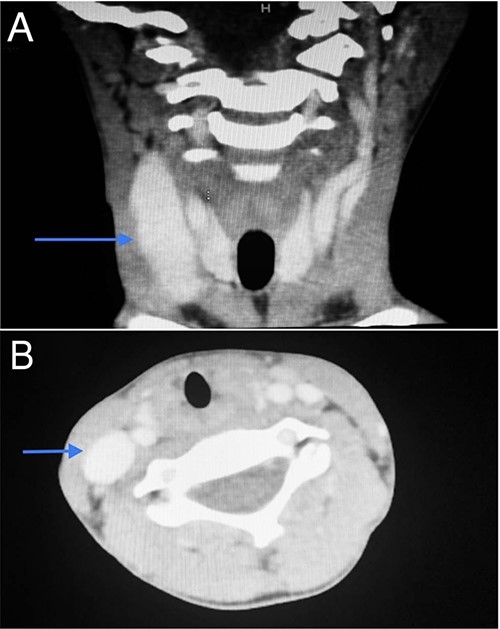

CT scan of the first patient in coronal view (A) and axial view (B) with blue indicate internal jugular phlebectasia.

CT scan of the second patient in coronal view (A) and axial view (B) with blue indicate internal jugular phlebectasia.